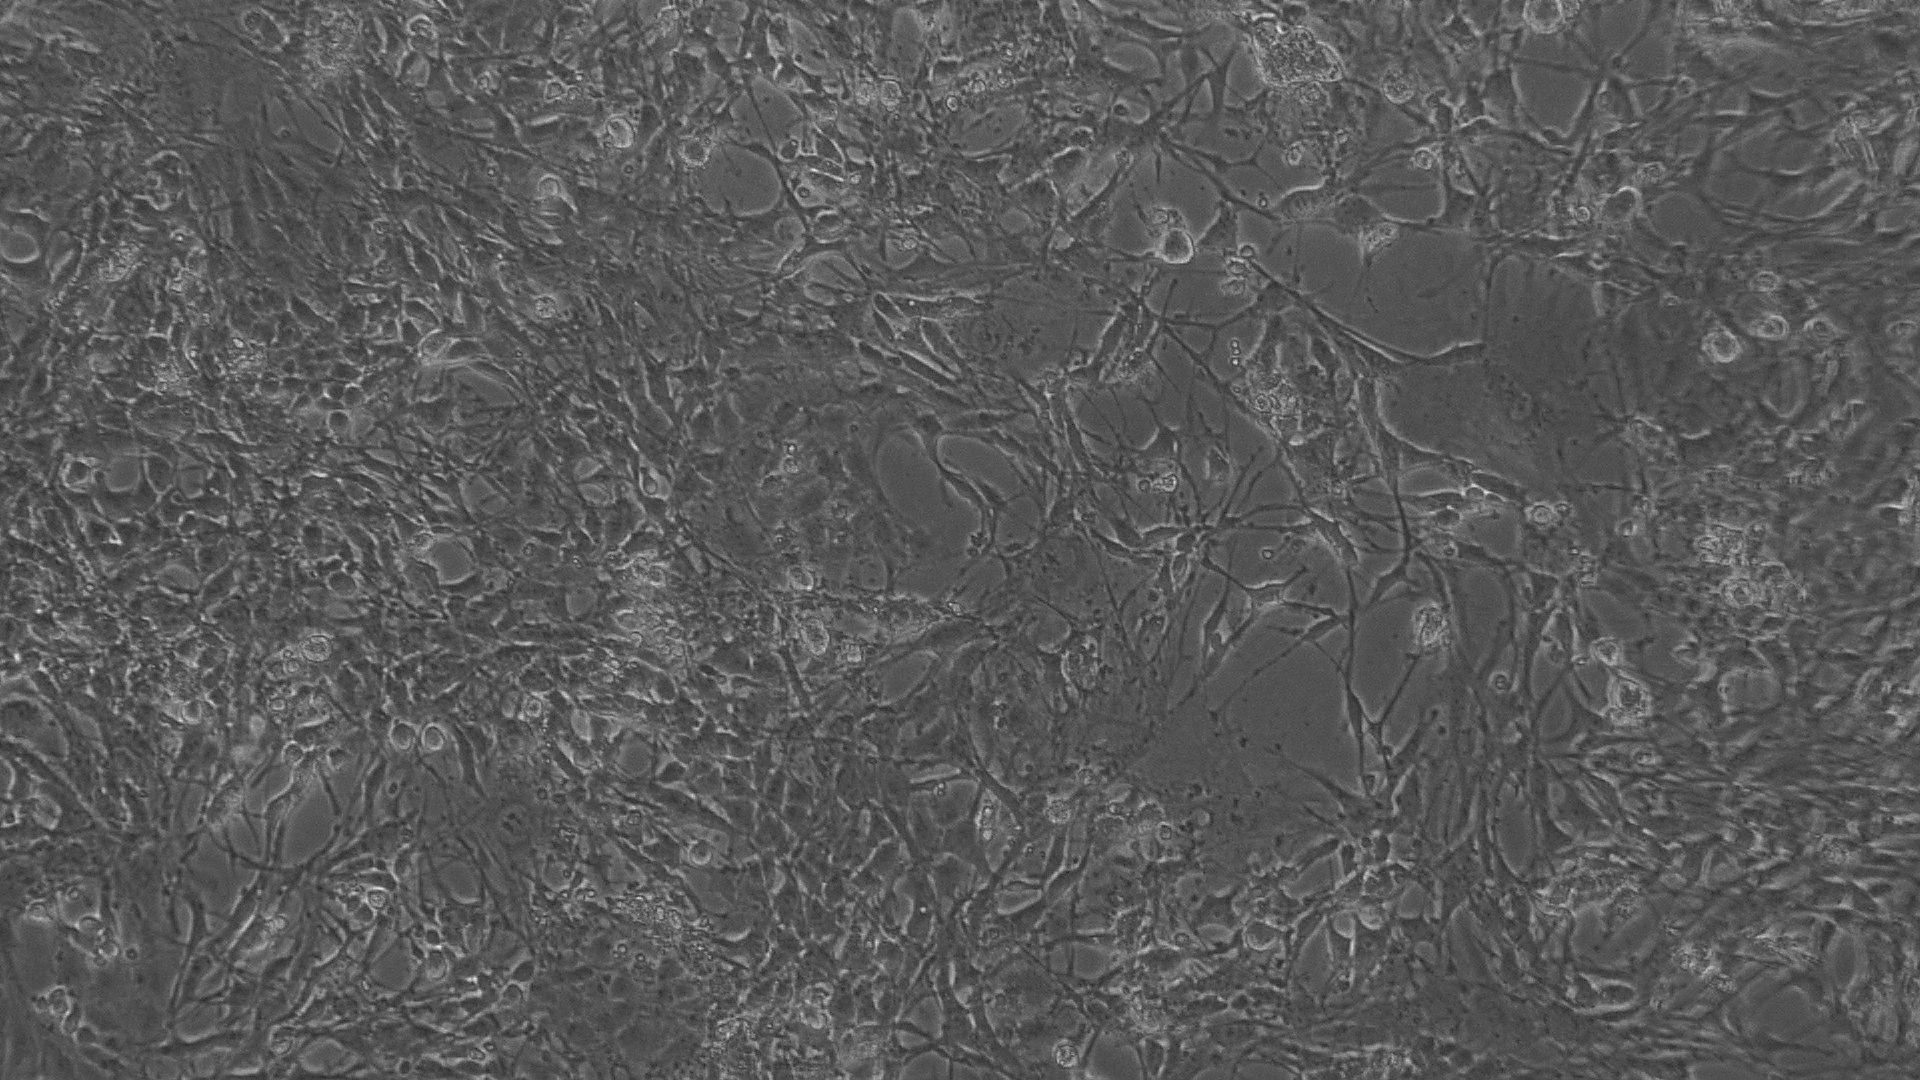

The entire plate was observed at an interval of every 24 h; up to 72 h in an inverted phase-contrast tissue culture microscope (Labomed TCM-400 with MICAPSTM HD camera) and microscopic observations were recorded as images. Any detectable change in the morphology of the cells, such as rounding or shrinking of cells, granulation, and vacuolization in the cytoplasm of the cells, were considered as indicators of cytotoxicity.

Fig. 6: Morphological changes showing inhibition of Hela cell lines by different concentrations of standard drug Doxorubicin. a: -ve control (95% ethanol), b: 0.097 µg/ml, c: 0.19µg/ml, d: 0.39 µg/ml, e: 0.78 µg/ml f: 1.56 µg/ml

In vitro anticancer actiivity of ethanolic extract of leaves of Pothos scandens Linn. was evaluated against HeLa and MCF 7 cell lines. The viability of cells was evaluated by direct observation of cells by an Inverted phase contrast microscope and MTT assay method. The morphological changes in HeLa and MCF 7 cells after treatment with the extract and standard doxorubicin are shown in fig. 5, 6, 7 and 8. The IC50 values are shown in table 4.